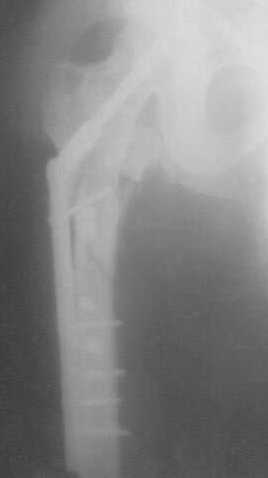

Re: Перелом вертлужной впадины и бедер

Я тоже считаю, сперва необходимо разобраться с переломаной и деформированой вертлужной впадиной, одномоментно устравнить вывих головки бедренной кости, с фиксацией диафиза (чем там у Вас есть), а остальное после активной подготовки больного. С уважением А.Леспович